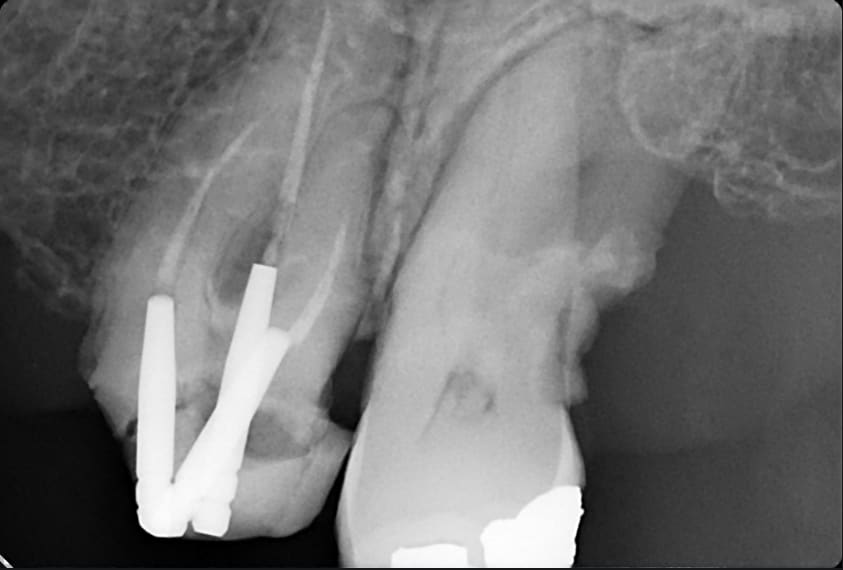

Ici une 37, complètement asymptomatique après un "soin" remontant à 5 ans...

Image extraite d'une pano.

Osons ! Osons !

En place depuis 10 ans. Aucune mobilité.